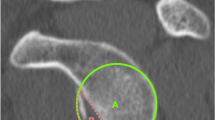

The glenoid surface of ten dried cadaveric scapulae (with intact surface) was measured by CT and laser methods (Fig. 1). Inclusion criteria for anatomical specimens were the presence of a whole glenoid bone surface and integrity of the glenoid bone edge. Scapulae with an impaired glenoid surface or damaged edge were excluded from this study.

Laser measurement

A laser probe for optical scanning system (CAM2, Faro Technologies, Lake Mary, www.faro.com) was used to measure the glenoid area. This certified high-precision device provides measurement of surfaces and volumes with a precision of 10−6 meter. A laser probe on the top of a seven-axis robotic arm allows detection of surface features of the scanned objects via coupled registration of laser feedback and robotic arm. A three-dimensional cloud of points is created and converted into the physical reconstruction by dedicated software (Geomagic Studio, version 10; Geomagic, Morrisville, NC; hyperMILL, Open Mind Technologies, Needham, MA; and Autodesk 3ds Max, Autodesk, San Rafael, CA). The volumetric model is stored as Initial Graphics Exchange Specification (IGES file). Geometric features of this volumetric model can be calculated. Laser calibration was provided by the manufacturer by means of metal cylinder with a nominal diameter of 25.420 mm. The technical data supplied with the unit: accuracy of the measurement (diameter) (0.01 mm) and repeatability (0.022 mm). The glenoid surface of each specimen was laser-scanned by a mechanical engineer with a 4-year experience in CAM2 practice in the setting of mechanical parts 3D scanning and reproduction. The same reader measured glenoid surfaces on an IGES file using CAD software (AutoCAD® 2013), according to the Pico technique, and then tracing a circumference of the circle in the region of interest (ROI) in a sagittal plane. This employs a circumferential region of interest (ROI) that is placed on the inferior glenoid rim using a 3-D model (Fig. 3b, c) [7, 12]. Measurements were performed twice, 2 weeks apart.

The inscription of the inferior glenoid in a circle, which occurs on flat MPR images, did not correspond to the real anatomy of the glenoid surface, which, besides being curved, is difficult to compare to a circle, thus reducing the accuracy of the CT Pico method (Fig. 3c–d).

One normal glenoid specimen (a) and the model derived from laser scanning (b) are illustrated. The measurement of the glenoid surface by the CT Pico method is reported on laser (c) and CT data (d). Note as a part of the anterior glenoid is not included in the circle using the CT Pico method (arrows in c and d). The inscription of the inferior glenoid in the circle, which occurs on flat MPR images (d), could not correspond to the real anatomy of the glenoid surface, which, besides being curved, is never comparable to a circle; this obviously reduces the accuracy of the CT Pico method

Since reliability of such a method appears to be weak when considering the glenoid surface of cadaveric specimens, it is probably not accurate for measuring the amount of bone loss in cases where the glenoid is deficient (Figs. 3 and 4)